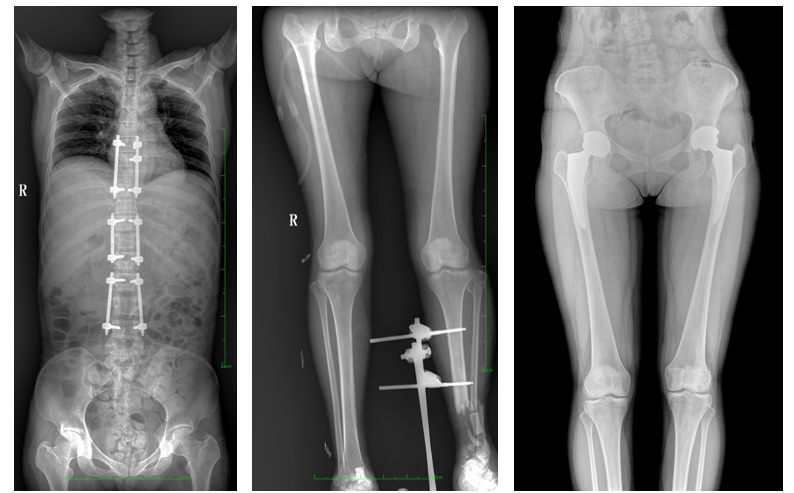

普愛醫(yī)療自主研發(fā),專為大視野臨床應(yīng)用打造的平板動態(tài)DR——PLX8600,圖像不拼接,有效簡化影像科室檢查流程,提高診斷精度,降低患者吸收的輻射劑量。與市面常規(guī)多張攝影再軟件拼接DR相比,PLX8600解決了拼接圖像存在密度不均勻,拼接處圖像配準和放大效應(yīng)等問題,輻射劑量是常規(guī)長骨軟件拼接DR的1/2或1/3,給患者更多關(guān)愛。

一、成像面積大。17"*34"有效視野,一次成像不拼接。相較于多張攝影再軟件拼接的DR設(shè)備,PLX8600解決了拼接圖像存在密度不均勻,拼接處圖像配準和放大效應(yīng)等問題,給臨床帶來了大視野影像解決方案,可一次性覆蓋全脊柱或雙下肢影像。

PLX8600大視野平板動態(tài)DR攝影速度快,患者可以更快地完成檢查,且單次攝影輻射劑量是常規(guī)多張攝影再軟件拼接DR的1/2或1/3,低劑量給患者更多關(guān)愛。

PLX8600大視野平板動態(tài)DR可在低輻射劑量下獲得患者站立位、臥位的高質(zhì)量影像。搭載自主研發(fā)的圖像均衡處理系統(tǒng),能夠很好的均衡人體不同厚度組織的影像,視野大,圖像清晰,層次豐富。如果您想采購這款產(chǎn)品,歡迎聯(lián)系我們,咨詢電話400-025-6366。